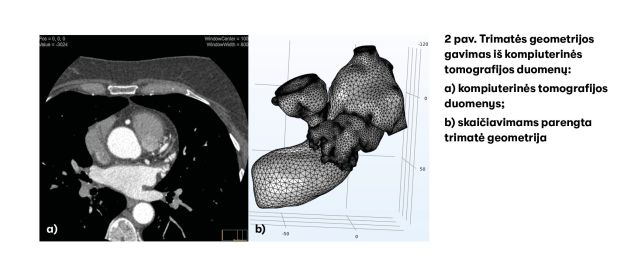

Šio projekto metu kuriamas matematinis modelis, kuris padėtų įvertinti trombo formavimosi greitį, atsižvelgiant į kairiojo prieširdžio apendikso geometriją. Norint atlikti kompiuterinius skaičiavimus, pirmiausia reikia gauti konkretaus paciento kairiojo prieširdžio apendikso kompiuterinės tomografijos duomenis. Tiriant kompiuteriniu tomografu kairiojo prieširdžio apendiksas skenuojamas plonais sluoksniais ir gaunami dvimačiai jo skerspjūvių vaizdai. Tuomet iš dvimačių vaizdų sudaroma trimatė kairiojo prieširdžio apendikso geometrija (2 pav.). Kai ši geometrija yra tinkamo kompiuteriniams skaičiavimams formato, atliekami skaitiniai eksperimentai.